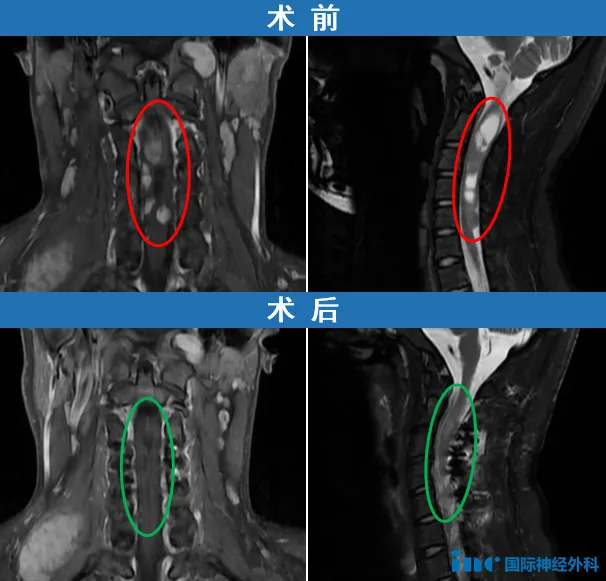

2025年10月23日,在苏州大学附属第四医院,帆帆顺利进行高位颈髓占位病变手术。帆帆的情况非常复杂,从颈髓内,到颈髓外,均有病变。术中,巴教授首先精准地切除了帆帆髓外多个由系带连接的鞘瘤,清除了第一重危机。而真正的挑战,在于髓内——与正常神经组织纠缠不清的肿瘤,边界模煳。巴教授在方寸之间耐心探寻,最终在肿瘤与正常组织之间找到分界,实现了令人满意的切除。